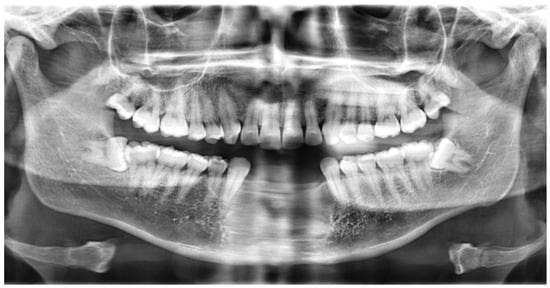

2. Case Report